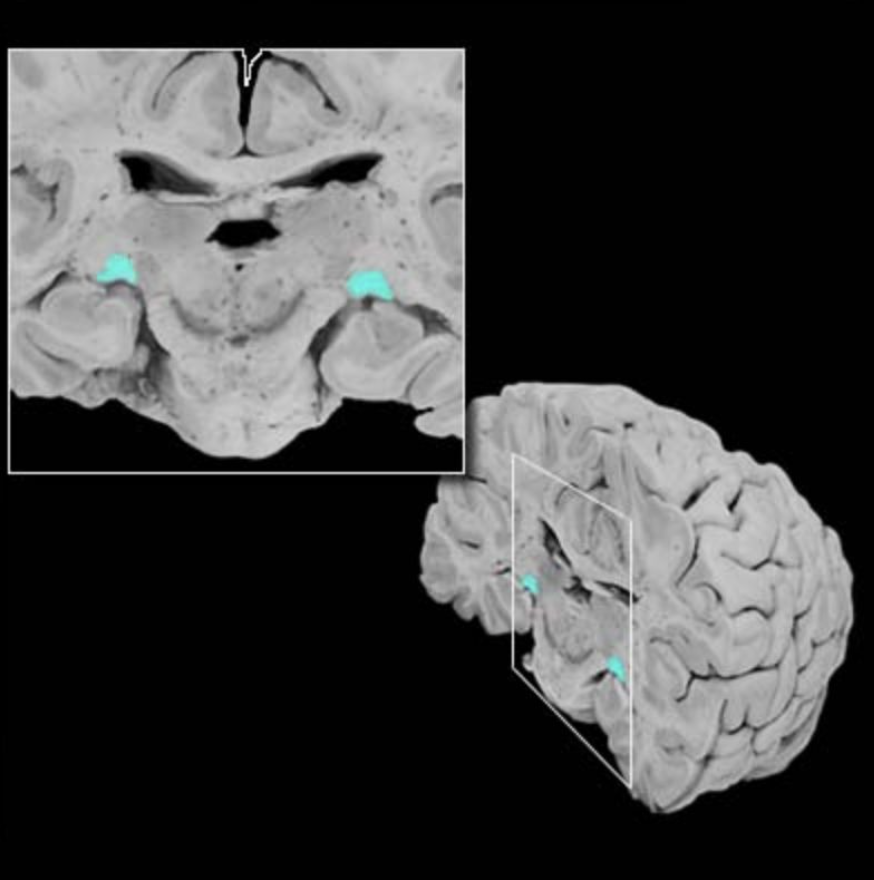

Dorsal column nuclei

Gracile nucleus and cuneate nucleus; contain the second-order sensory neurons that relay mechanosensory information from peripheral receptors in the body (excluding the face) to the thalamus via the medial lemniscus. The dorsal column nuclei are located in the lower medulla.

Dorsal spinocerebellar tract

Ascending sensory tract of the spinal cord originating in the dorsal nucleus of Clarke and terminating in the cerebellum (via the inferior cerebellar peduncle); this tract conveys proprioceptive information from the lower body.

Nucleus gracilis

Nucleus containing the second-order sensory neurons that relay mechanosensory information from peripheral receptors in the lower body to the thalamus via the medial lemniscus, located in the lower medulla (also called the "gracile nucleus"). The nucleus gracilis also relays visceral pain information from second-order neurons in the central spinal cord to the thalamus.